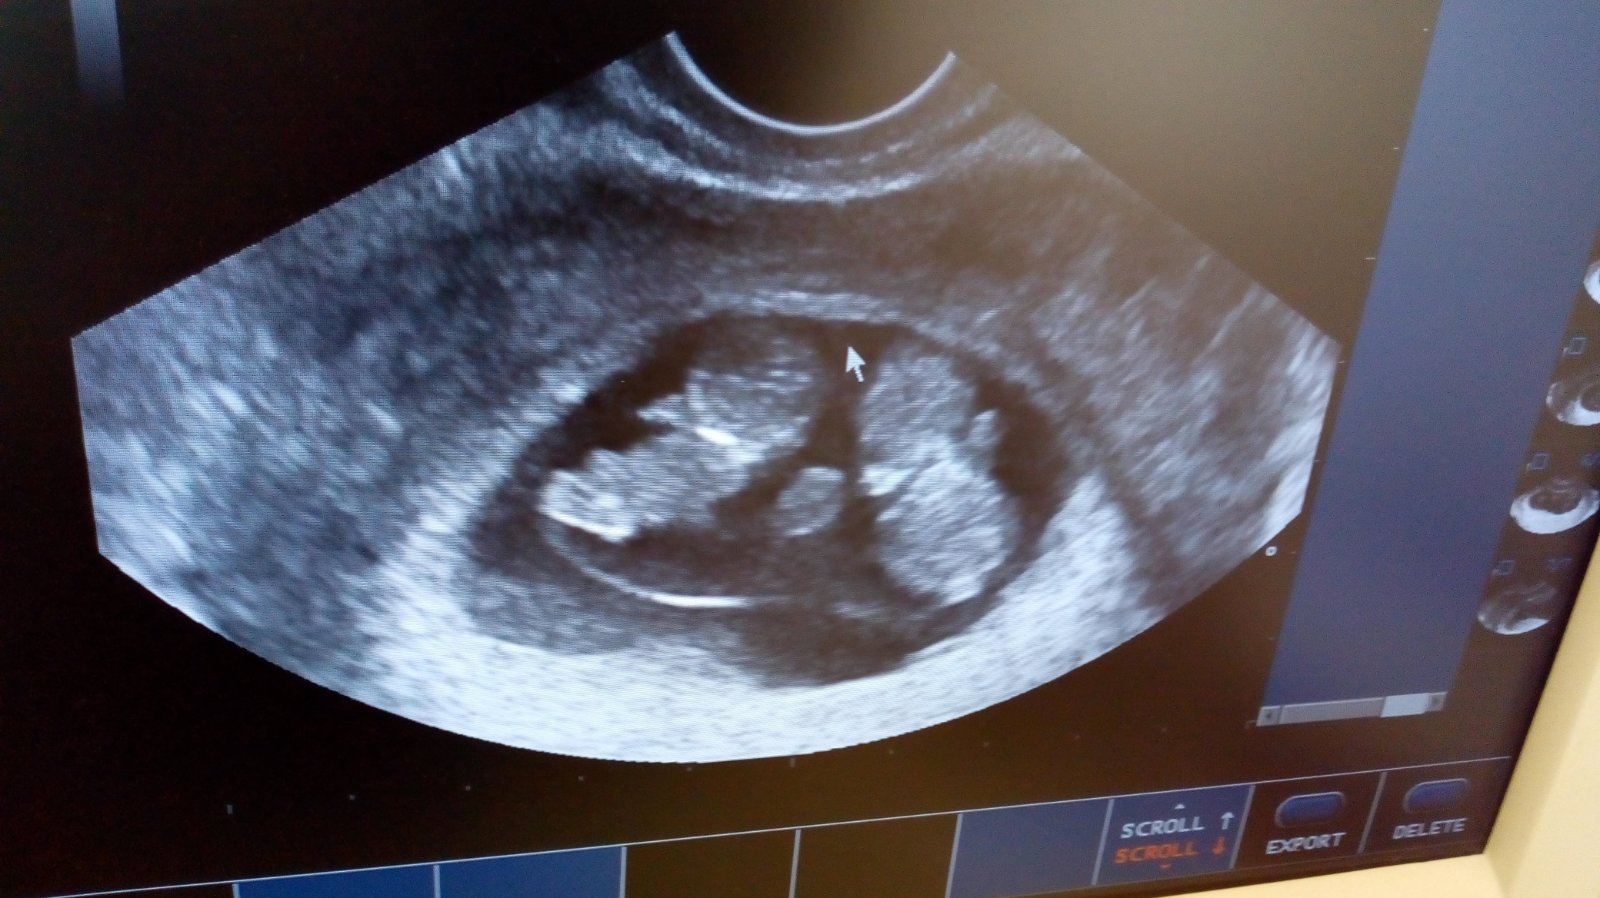

Najkrajší moment bol keď sa nám narodila naša dcérka... Pridala by som sem našu prvú spoločnú fotku, ale keďže je ešte z pôrodnej saly tak nieje vhodná 🤭 ale mojou druhou najkrajšiou spomienkou hneď po jej narodeni bol tento okamih 😍😍 a odvtedy vždy keď ich nájdem takto v objatí sa mi vtisnu slzy do očí od šťastia... Na nich dvoch spolu ma pohľad nikdy neomrzi a nič nenahradí to neopísateľné šťastie ❤️❤️

@sutaz môj najkrajší zážitok s mojou dcérou, bol už samotný pôrod. Naozaj po takých bolestiach to vystriedalo niečo nádherné a krásne moja dcérka prvýkrát v mojom náručí. Pre mňa neopísateľné nádherný zážitok